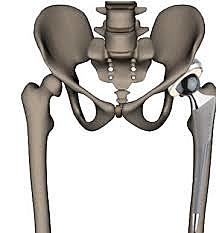

• Prótesis de cadera de recubrimiento

Prótesis de cadera de recubrimiento

Desarrollaron nuevos implantes como las modernas prótesis de recubrimiento, retomando la antigua idea de la prótesis de recubrimiento de Smith-Petersen

• minivástagos femorales

minivástagos femorales

se retomo la antigua idea de la prótesis de recubrimiento de Smith-con la utilización de minivastagos